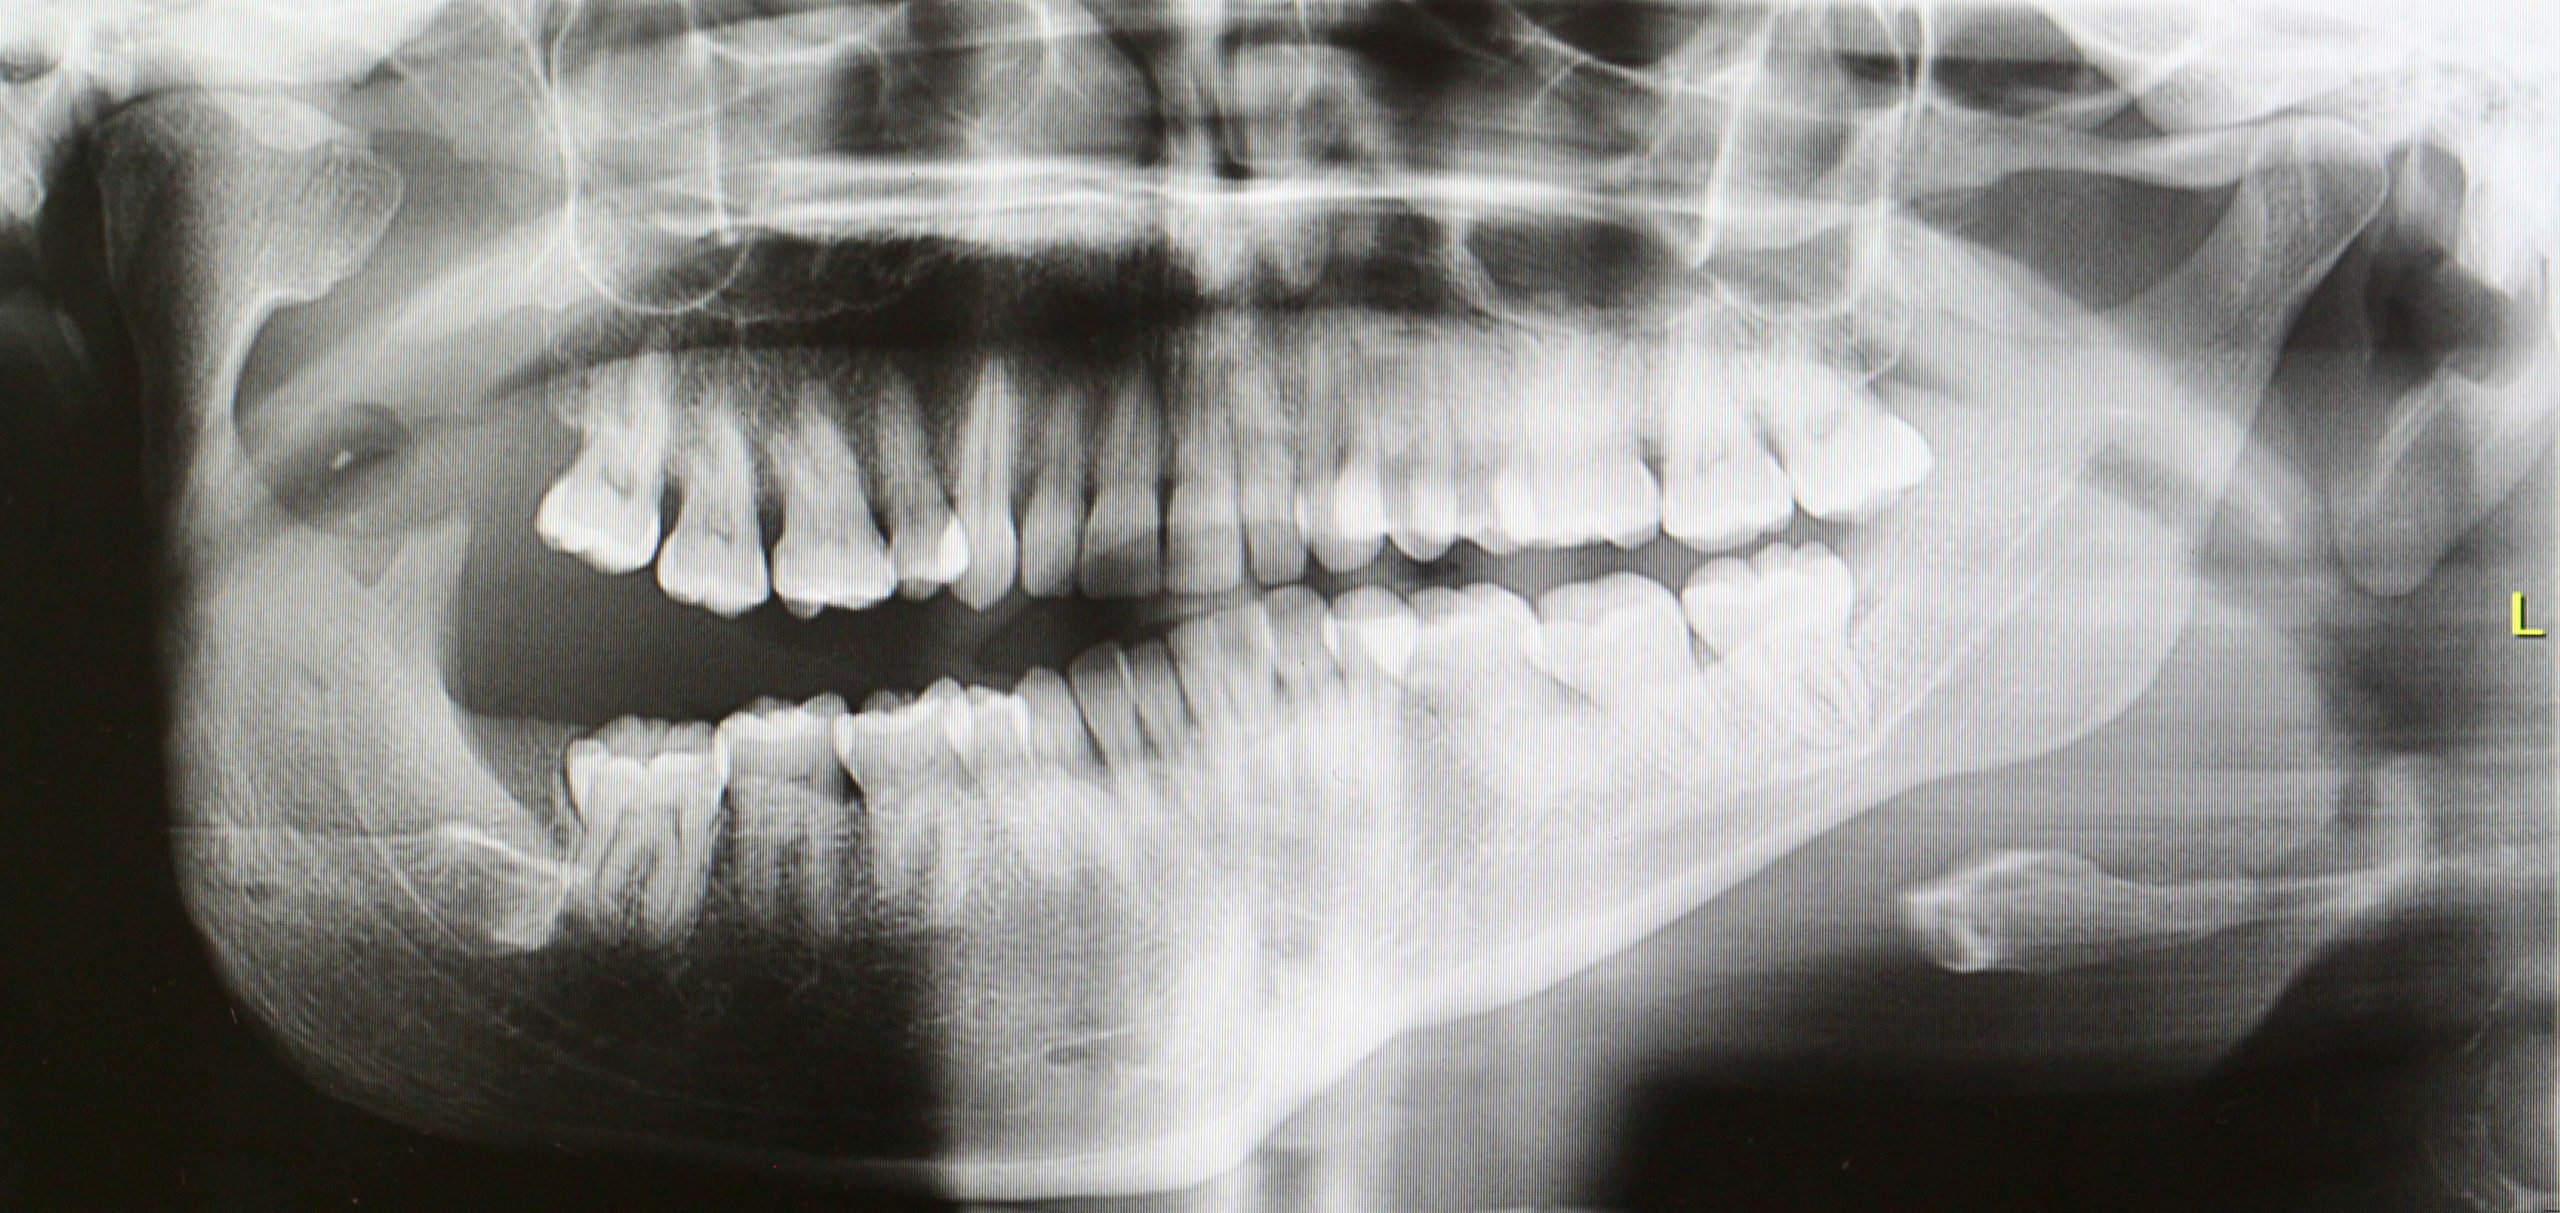

Diagnóstico: Desequilibrios Esqueléticos Maxilofaciales

La Cirugía Ortognática reposiciona el maxilar superior y la mandíbula buscando la mejor estética y armonía facial, junto con la correcta función masticatoria, respiratoria y del habla. Se corrigen disarmonías como la Retrusión Mandibular, el Exceso Vertical Maxilar o la Asimetría. Antes de la intervención, se realiza un estudio exhaustivo y una planificación virtual que asegura la precisión del movimiento óseo.